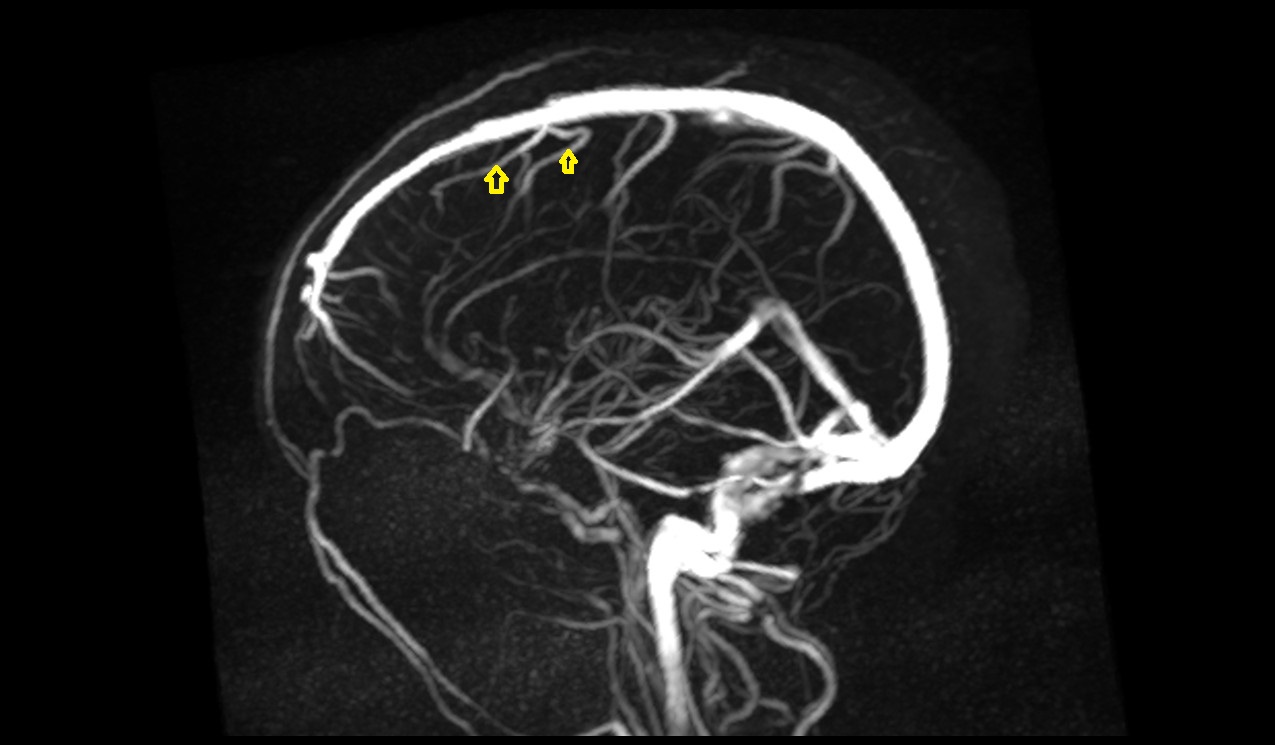

- Superficial cerebral veins

- Superior anastomotic vein

- Superior sagittal sinus

- Superior cortical veins